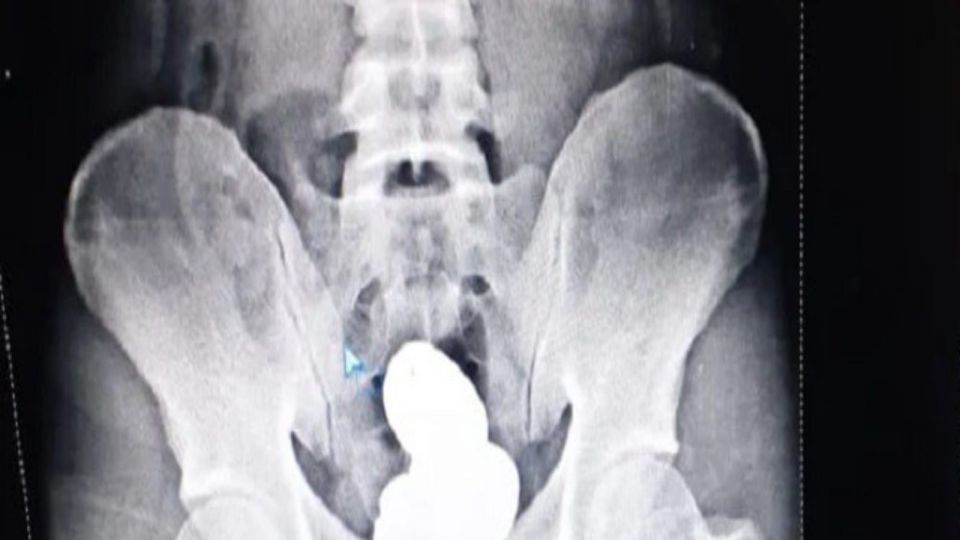

Everyone was stunned by the X-rays. The man had about 908 grams of gold in his rectum. The gold was poured into his stomach in the form of a paste. The paste was sold in four parts and packaged to hide in the rectum. After seeing the X-rays, the police conducted a rigorous interrogation in which he confessed to his allegations. He said he had inserted the gold paste into his rectum from the lower passage with incredible difficulty.

The man hid the gold paste in the rectum.